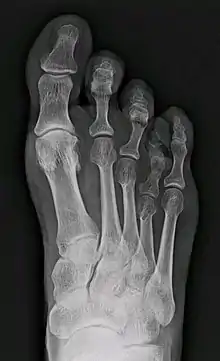

X-ray of congenital brachymetatarsia involving fourth metatarsal bone

It most frequently involves the fourth metatarsal. If it involves the first metatarsal, the condition is known as Morton's syndrome. Treatment is via a number of differing surgical procedures.[3]